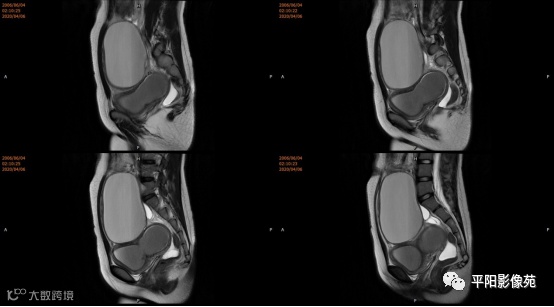

宫颈缺如、阴道闭锁

阴道闭锁

(1) 阴道闭锁I型:对应AFS系统中的阴道下段闭锁,阴道上段及子宫发育正常,内膜功能好

(2) 阴道闭锁II型:对应AFS系统重的阴道完全闭锁,常合并子宫颈闭锁,子宫体发育正常或有畸形,子宫内膜功能稍差

4.MRI检查 对软组织分辨率好,能够清晰区分子宫及阴道,对子宫内膜、结合带、肌层可清晰分辨;能明确子宫、宫颈、阴道结构异常的部位、范围、性质等。宫腔内经血潴留时,宫腔内见短T1长T2信号。